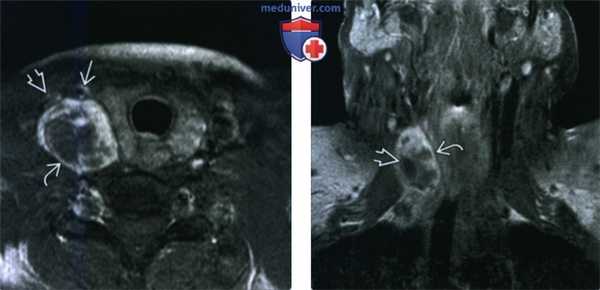

(Слева) При МРТ в аксиальной плоскости на Т1ВИ в медиальной головке икроножной мышцы определяется небольшое овальное объемное образование. Образование характеризуется изоинтенсивным и слабогиперинтенсивным сигналом по сравнению с мышцами, что затрудняет выявление его контуров.

(Справа) У этого же пациента при МРТ в аксиальной плоскости на Т2ВИ в режиме FS визуализируется объемное образование с гетерогенно гиперинтенсивным сигналом по сравнению с мышцами. В классических случаях при МРТ с чувствительными к жидкости последовательностями выявляется симптом «мишени» (гиперинтенсивная зона по периферии и гипоинтенсивная зона в центре), однако в этом случае он отсутствует. (Слева) При МРТ с контрастным усилением в аксиальной плоскости на Т1ВИ в режиме FS определяется гомогенное контрастирование объемного образования. Выраженность контрастирования шванномы варьирует от его отсутствия до интенсивного контрастирования гомогенного или гетерогенного характера. Диффузный характер контрастирования, как в данном случае, при шванноме встречается чаще, чем при нейрофиброме.